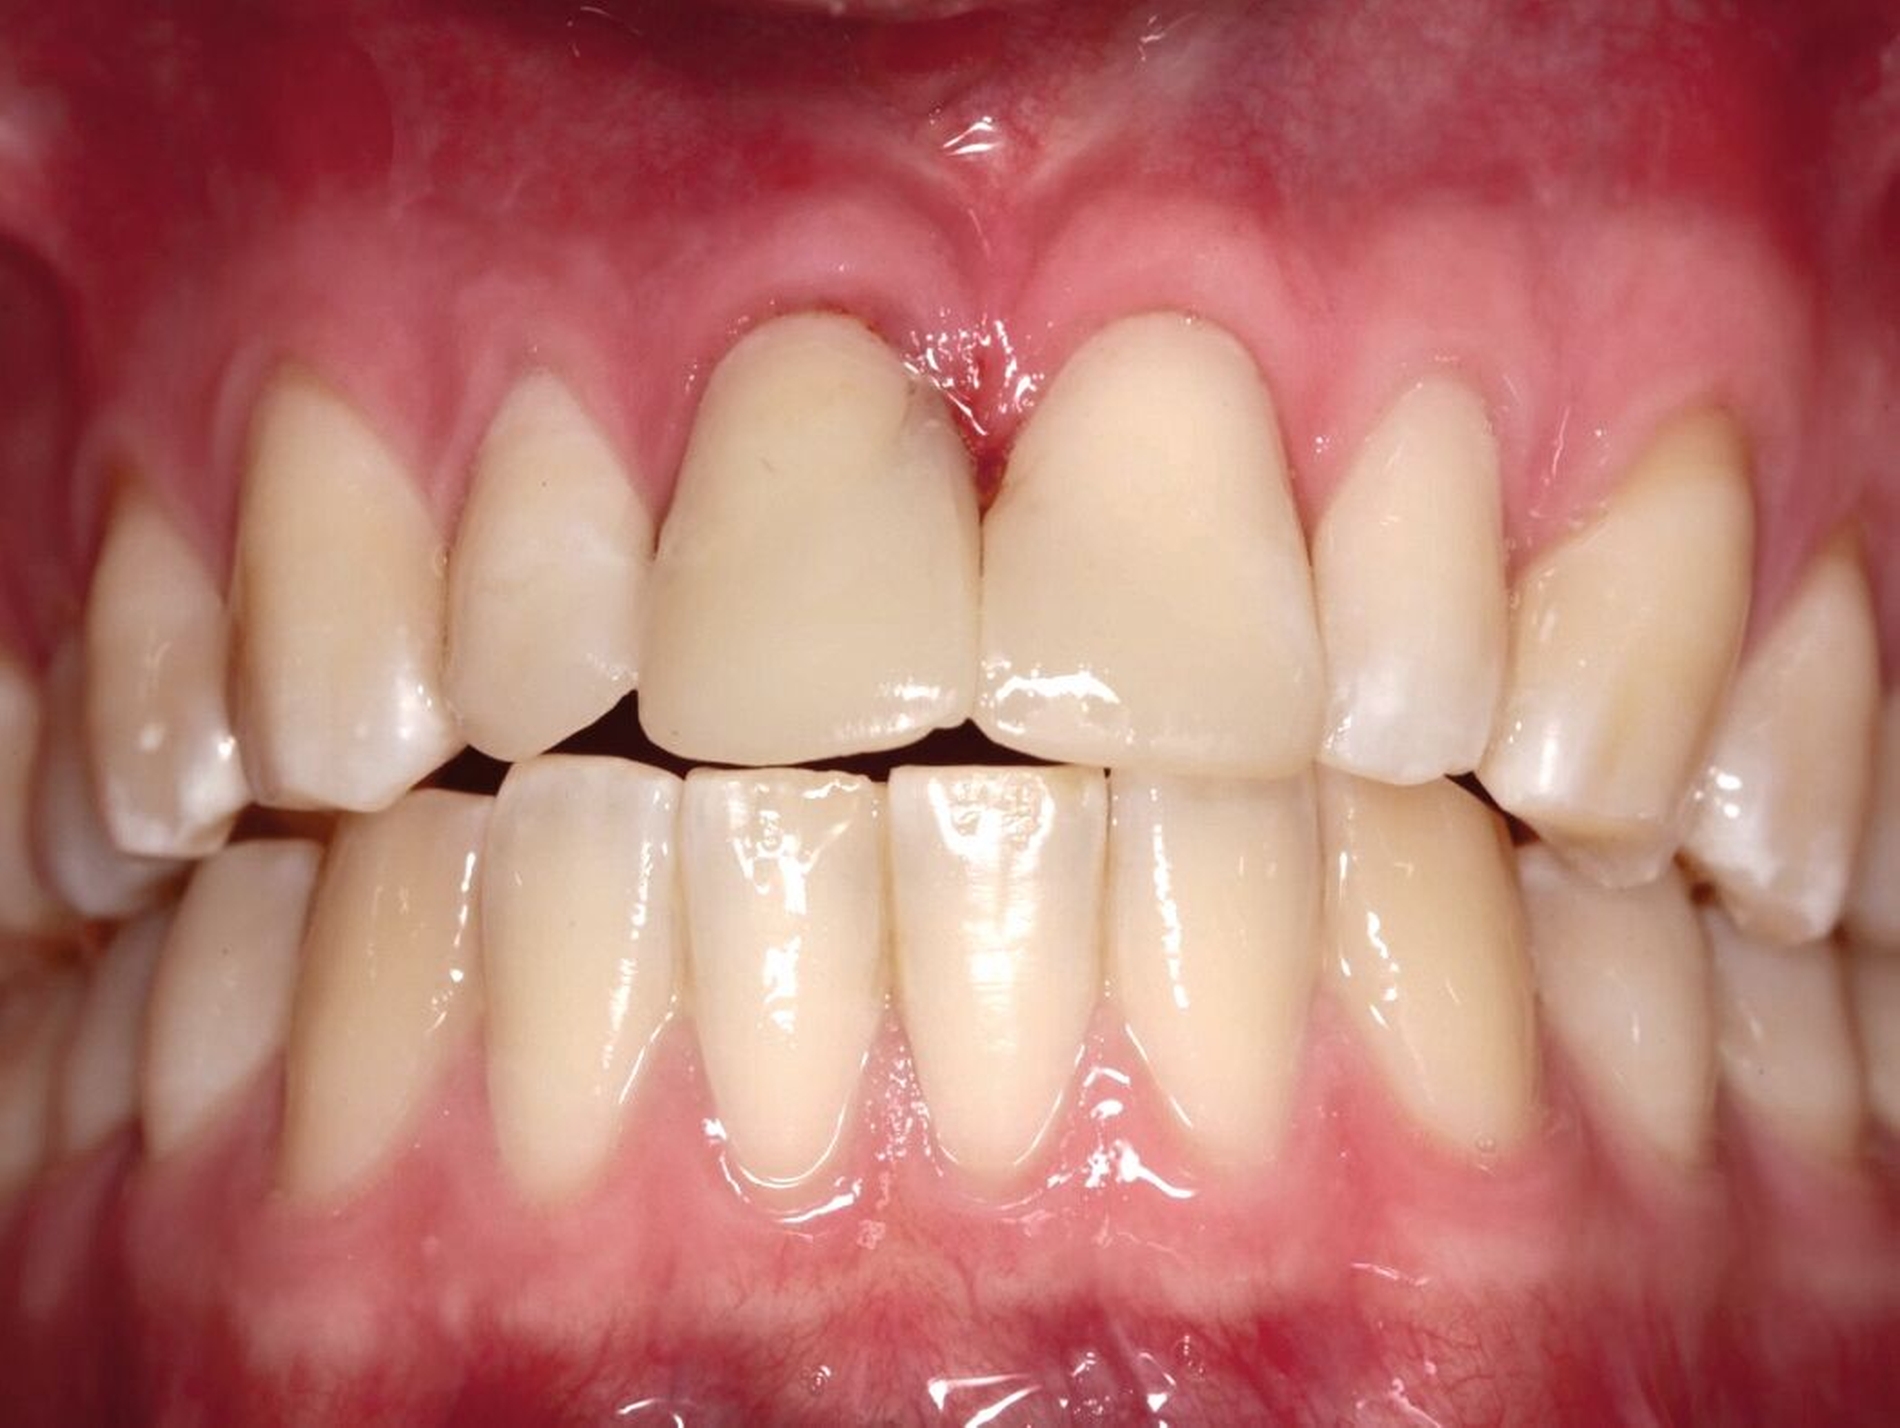

Die Zähne 11 und 21 wurden nach Abschluss der kieferorthopädischen Behandlung mit Lithiumdisilikat-Keramikkronen versorgt (Abbildungen 14 bis 16). Durch die Extrusion waren das Fassen der Frakturkante und die Etablierung des Ferrule-Effekts nun ohne Probleme möglich. Die Eingliederung der Arbeit konnte unter absoluter Trockenlegung erfolgen. Die nach dem Einsetzen angefertigte Einzelzahnaufnahme zeigt die präzise Adaptation der Kronen sowie Umbauprozesse des Alveolarkamms. Drei Jahre nach Therapieabschluss zeigt sich eine suffiziente klinische Situation (Abbildung 17).